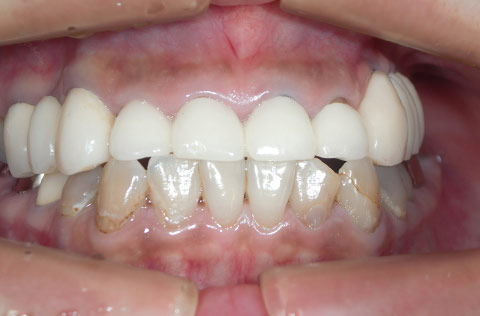

奥歯がなく、前歯は重度の歯周病だった。インプラントを含む包括的治療で、審美性と機能を回復したケース。

上あご前歯の咬耗と、左奥歯が全部欠損しているケース。インプラントを含む包括的治療で、見た目と機能を回復した。